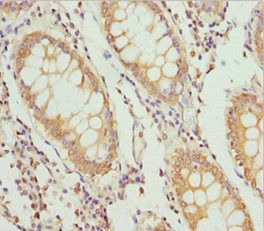

Immunohistochemistry of paraffin-embedded human colon cancer using CSB-PA864016DSR1HU at dilution of 1:100